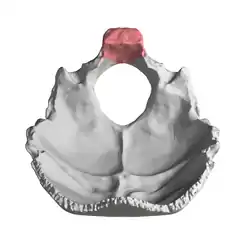

Occipital bone inner surface (basilar part is shown in red) | |

Occipital bone. Basilar part shown in red.

Occipital bone. Basilar part shown in red. Human skull seen from below. Basilar part shown in red.